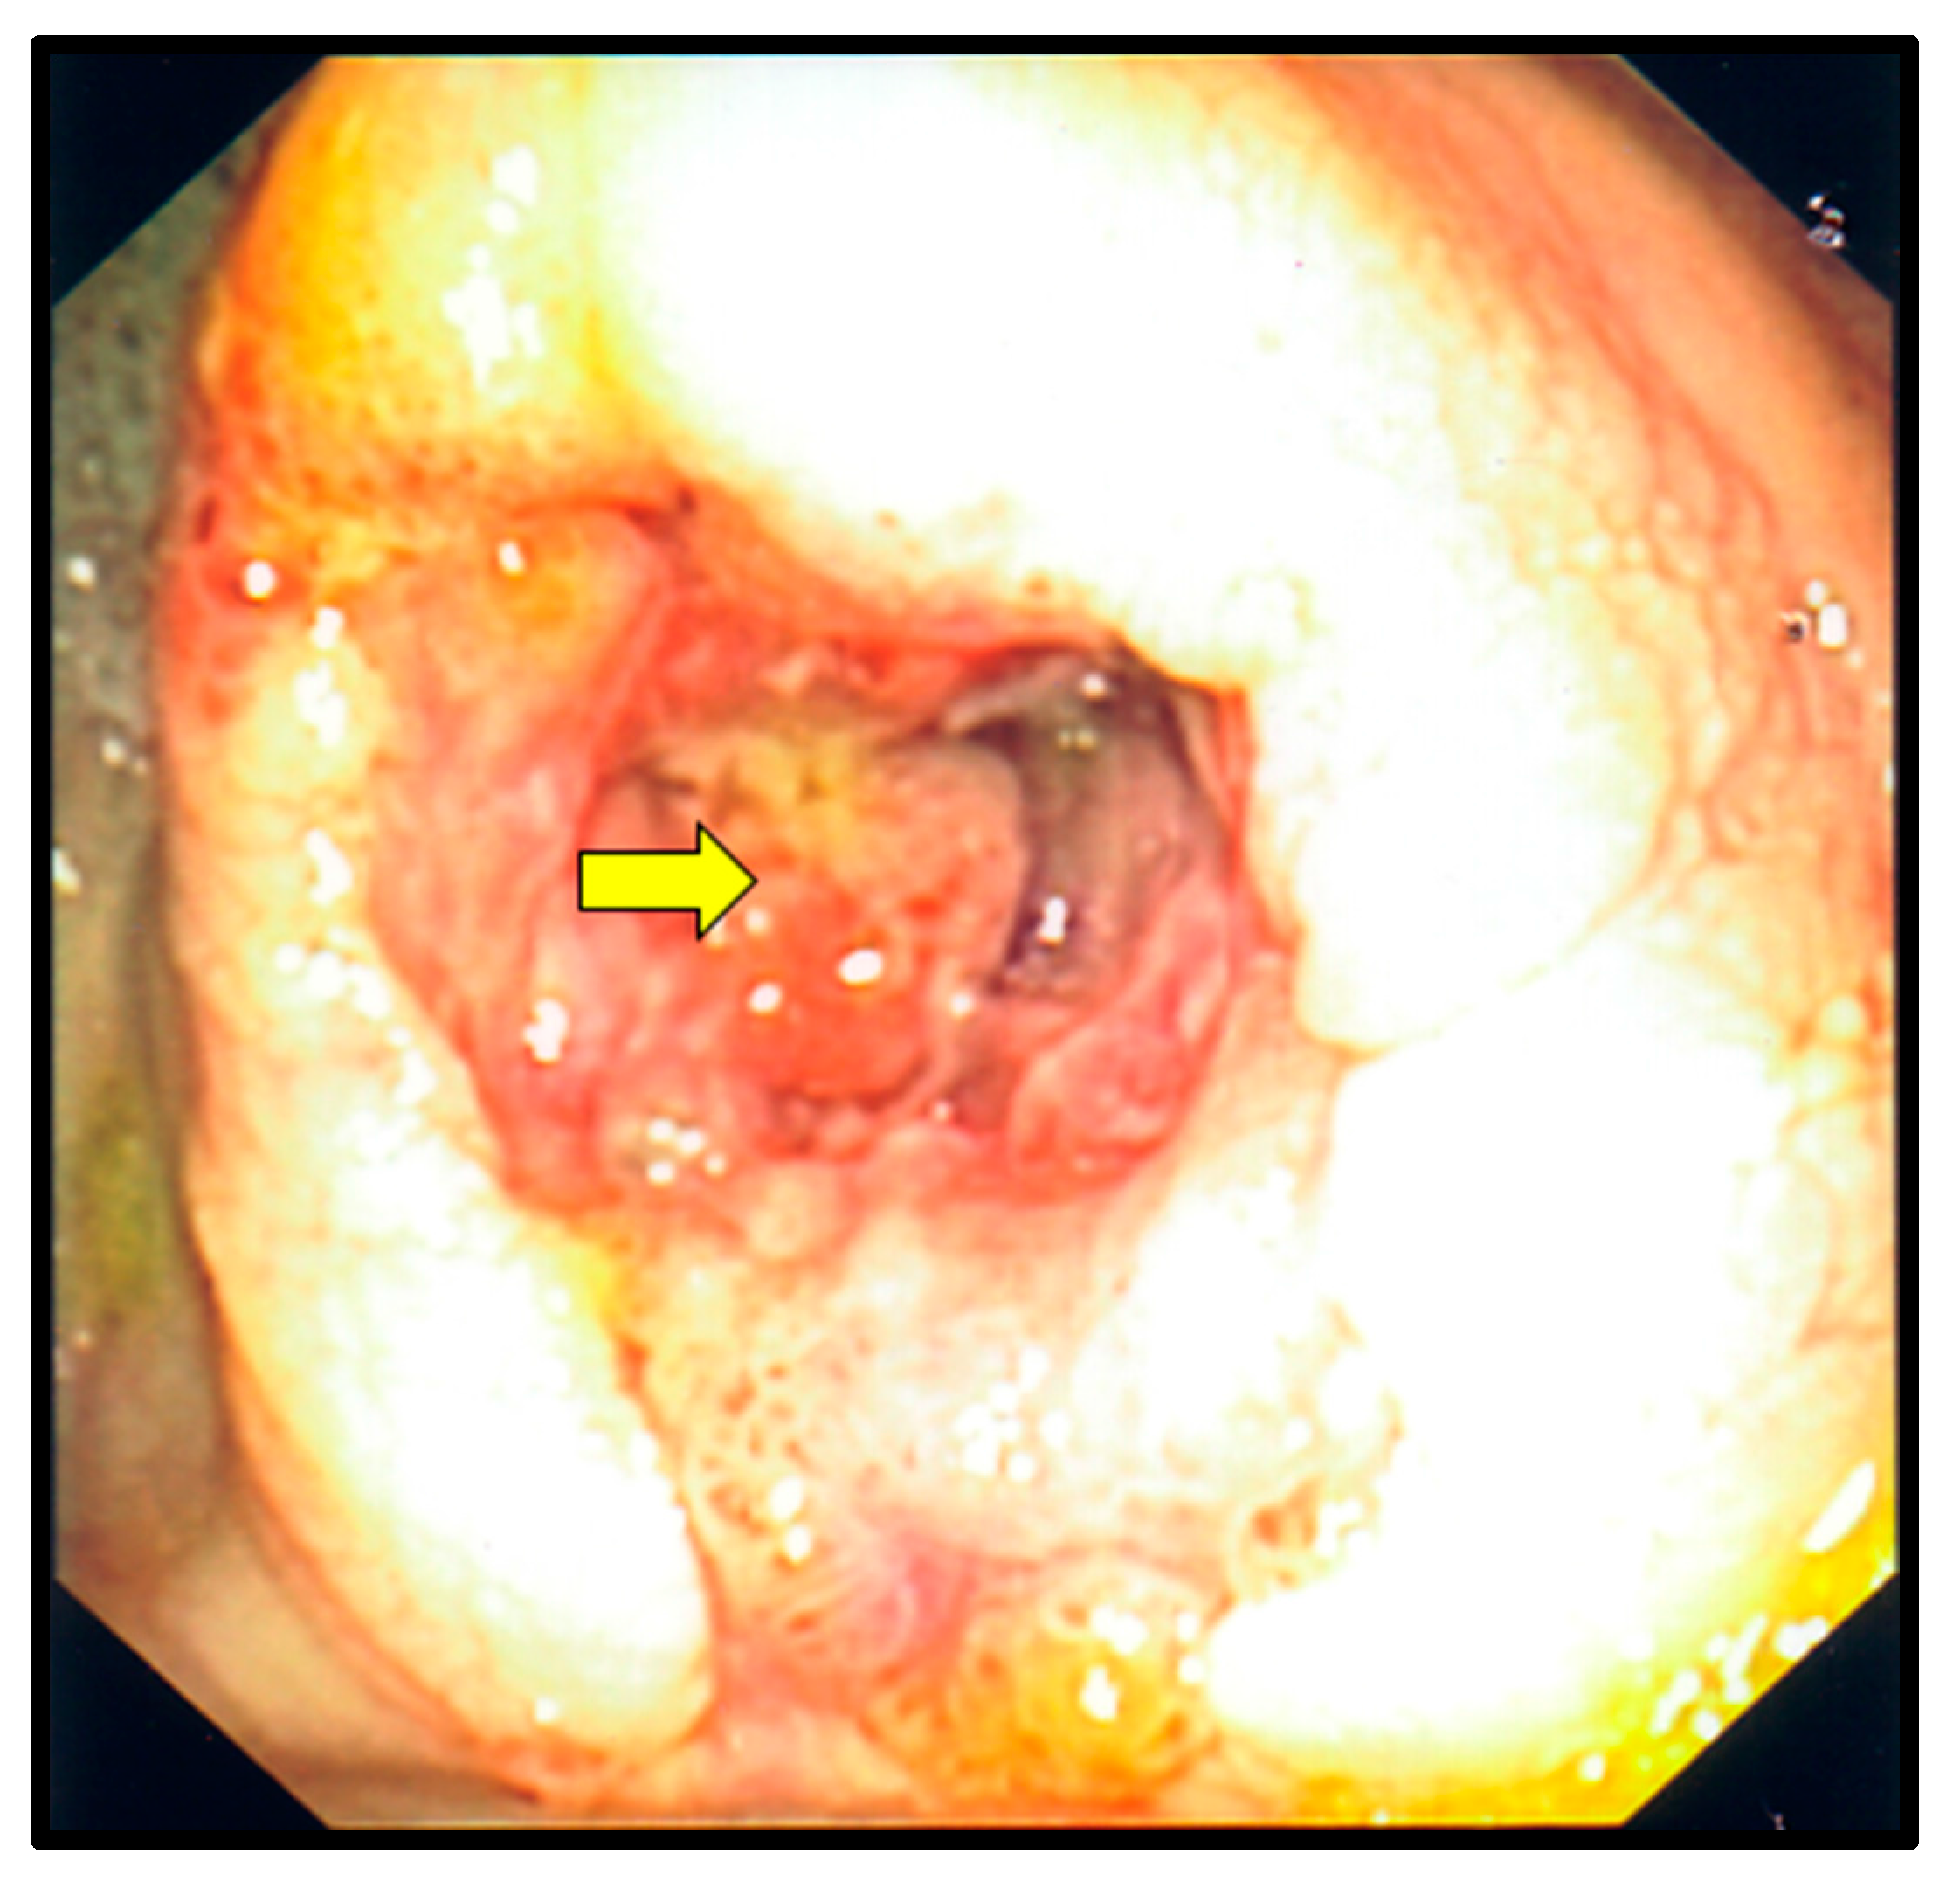

Figure 4.

Colonoscopy. The yellow arrow points to a large ulcerative mass in the cecum, which was secondary to gastrointestinal histoplasmosis.